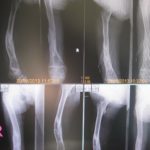

Consultation de Sarkini à l’hôpital orthopédique des enfants de Banepa

- Un suivi médical orthopédique important pour une jeune fille